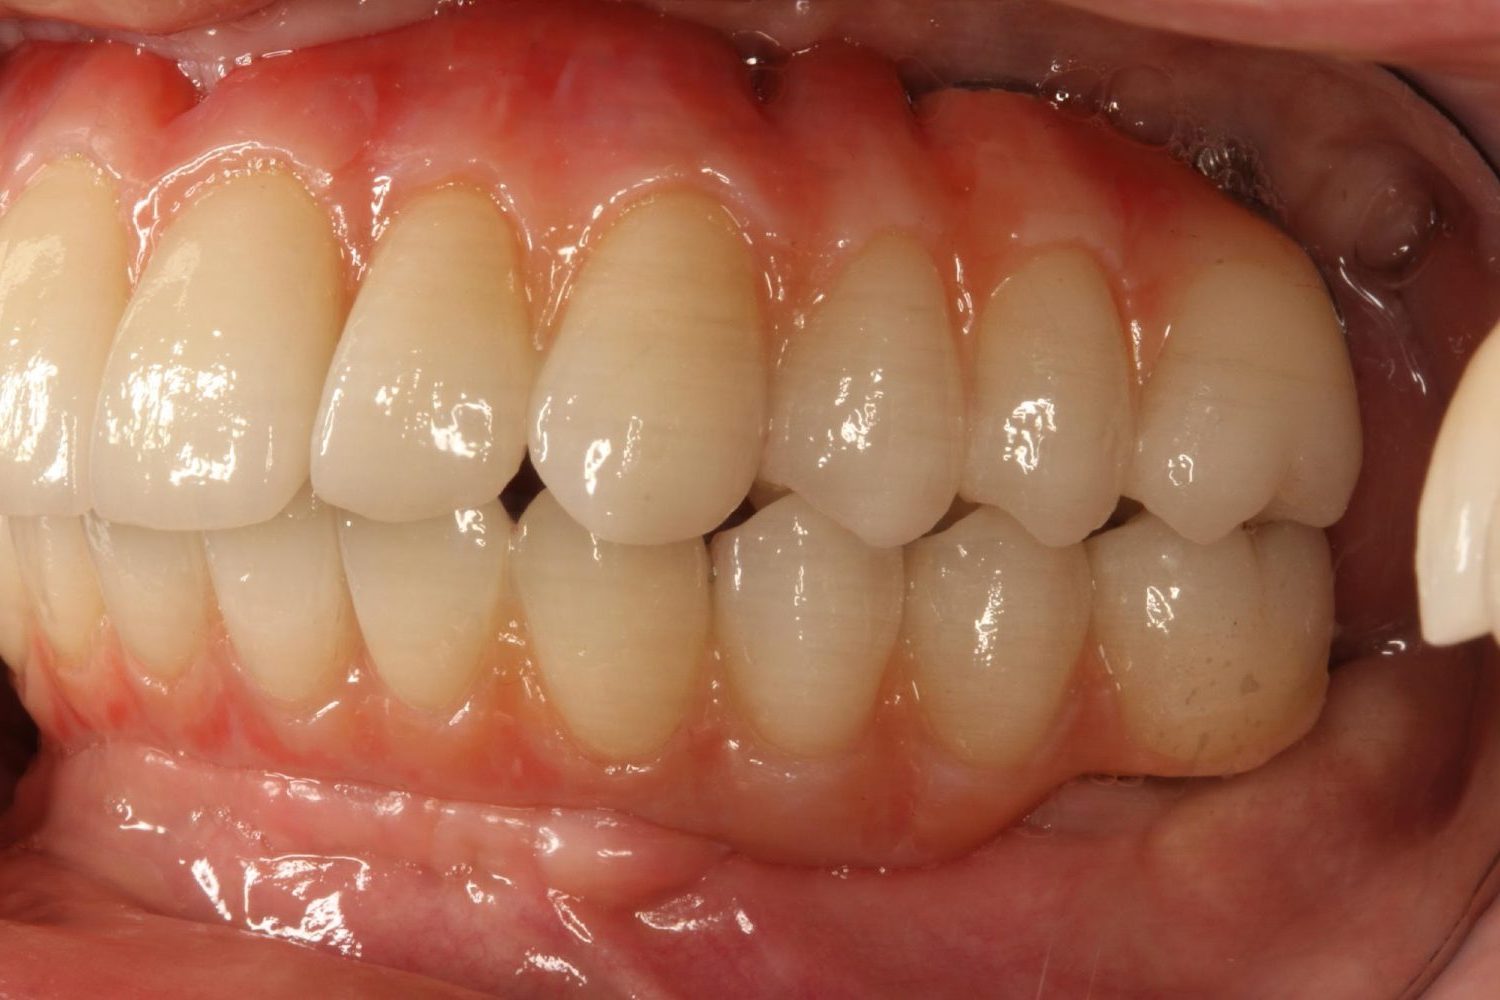

インプラント治療の症例紹介④

Before

After

主訴

義歯による疼痛

治療内容

下顎舌側に骨隆起があり義歯困難な状態。保存不可能な歯の抜歯を行い、インプラントを埋入し咬合再構成を行った。

治療費

2,851,200円(税込)

治療期間

29ヶ月

通院回数

26回

想定されたリスク

※咬合力の強い方なので、予防的にマウスピースの装着が必要。インプラント周囲炎の恐れがありました。

濱 仁隆先生

浜歯科

歯の欠損の対合歯の挺出等を修正し咬合平面を揃え咬合再構成を行った症例。